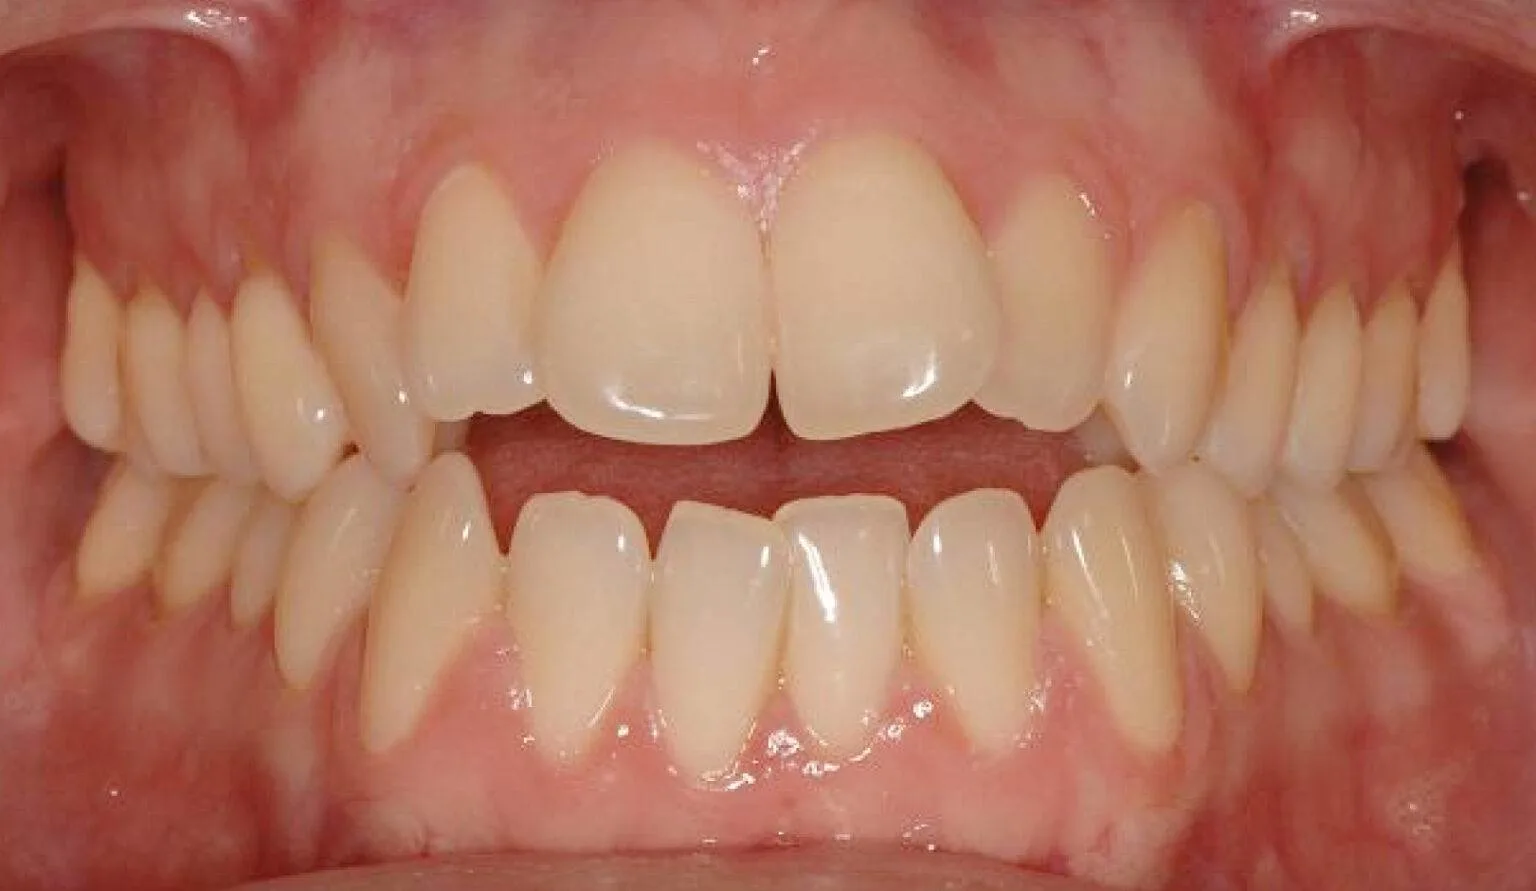

Before overcrowding treatment at SmileBox Clinic After overcrowding treatment at SmileBox Dental Clinic